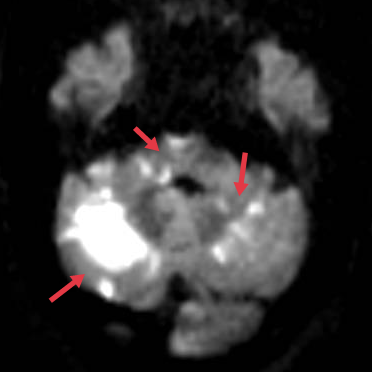

2023-05-16【医疗技术】神内卒中团队开通基底动脉1例

4月26日,10:47分:59岁男性王某,以“意识障碍40分钟”入我院,专科查体可见患者呈昏睡状态,反应迟钝,吐字不清,双眼向右凝视,四肢肌力5-级,NIHSS评分7分。 卒中... -